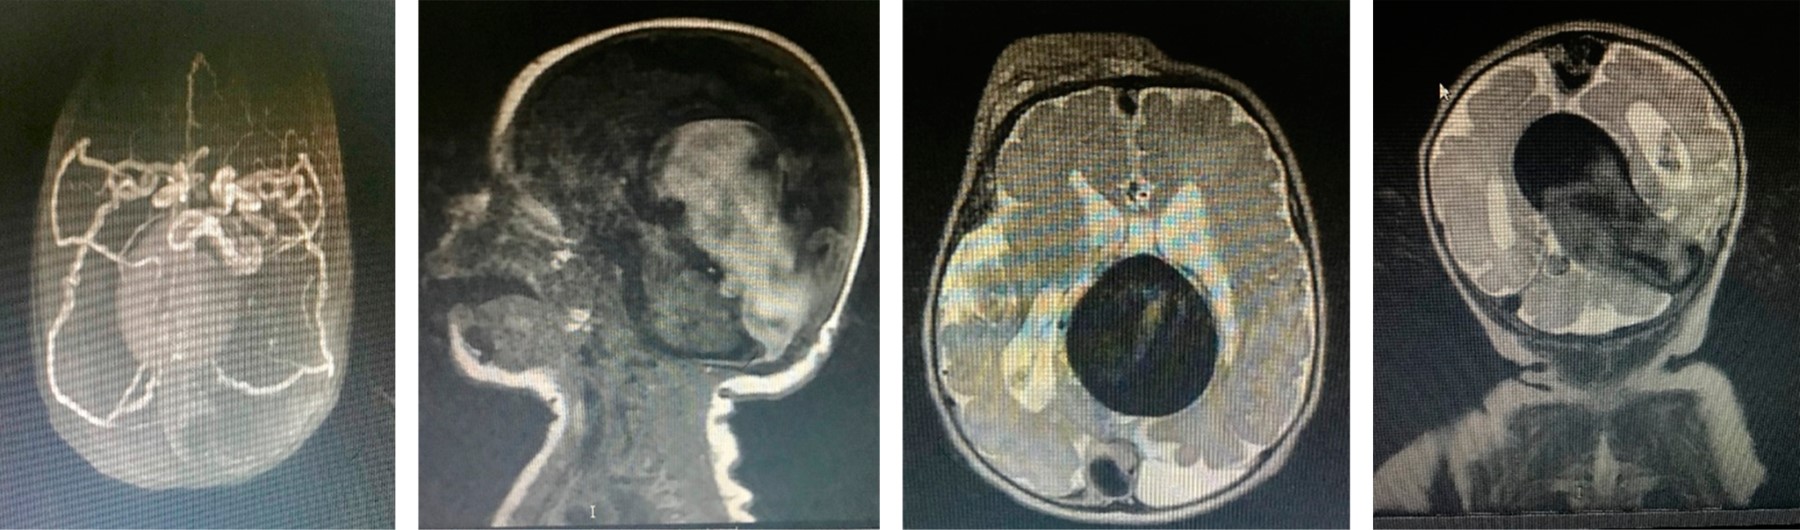

RN masculino, primer producto de una madre de 19 años. A las 25 semanas de gestación (SDG), por ecografía gestacional, se identificó un hematoma supratentorial. Mientras que a las 33.6 SDG, por sospecha de holoprosencefalia se realizó una neurosonografía fetal, en la cual se encontró imagen anecoica en forma de reloj de arena, de dimensiones de 74 × 37 mm, vascularizada, sugestiva de malformación venosa tipo aneurisma de la vena de Galeno (Figura 1). A las 35 SDG por ecocardiografía se detectó cardiomegalia con sobrecarga de cavidades derechas.

Figura 1